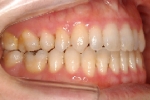

カテゴリー:開咬(overbiteがマイナスのもの)

| 治療後3年経過時

出題の意味:開咬とは奥歯がしっかり咬んでも(完全に閉じても)、前歯が上下的に重ならないケースを言う。Overbiteがマイナスというのは全然重なっていないということを示しており、マイナス方向に数字が大きくなるほど症状はきつくなる。つまり完全に閉じているのに、前歯の隙間から舌が見えるような状態と言うこと。この症状は、舌や唇の筋力や動かし方に原因があるので、歯を矯正するだけではだめで、舌や唇の動かし方を正常にしないと後戻りを起こしやすい。専門医の試験では、治療後2年以上経過した資料を添付して、経過が良好であることを証明しないといけないので、後戻りしやすいこのケースは難易度が高いといえる。舌や唇の動かし方をトレーニングするのは、医院スタッフ(主に筋機能訓練療法を担当する歯科衛生士)であるので、医療機関の総合力が問われる項目である。